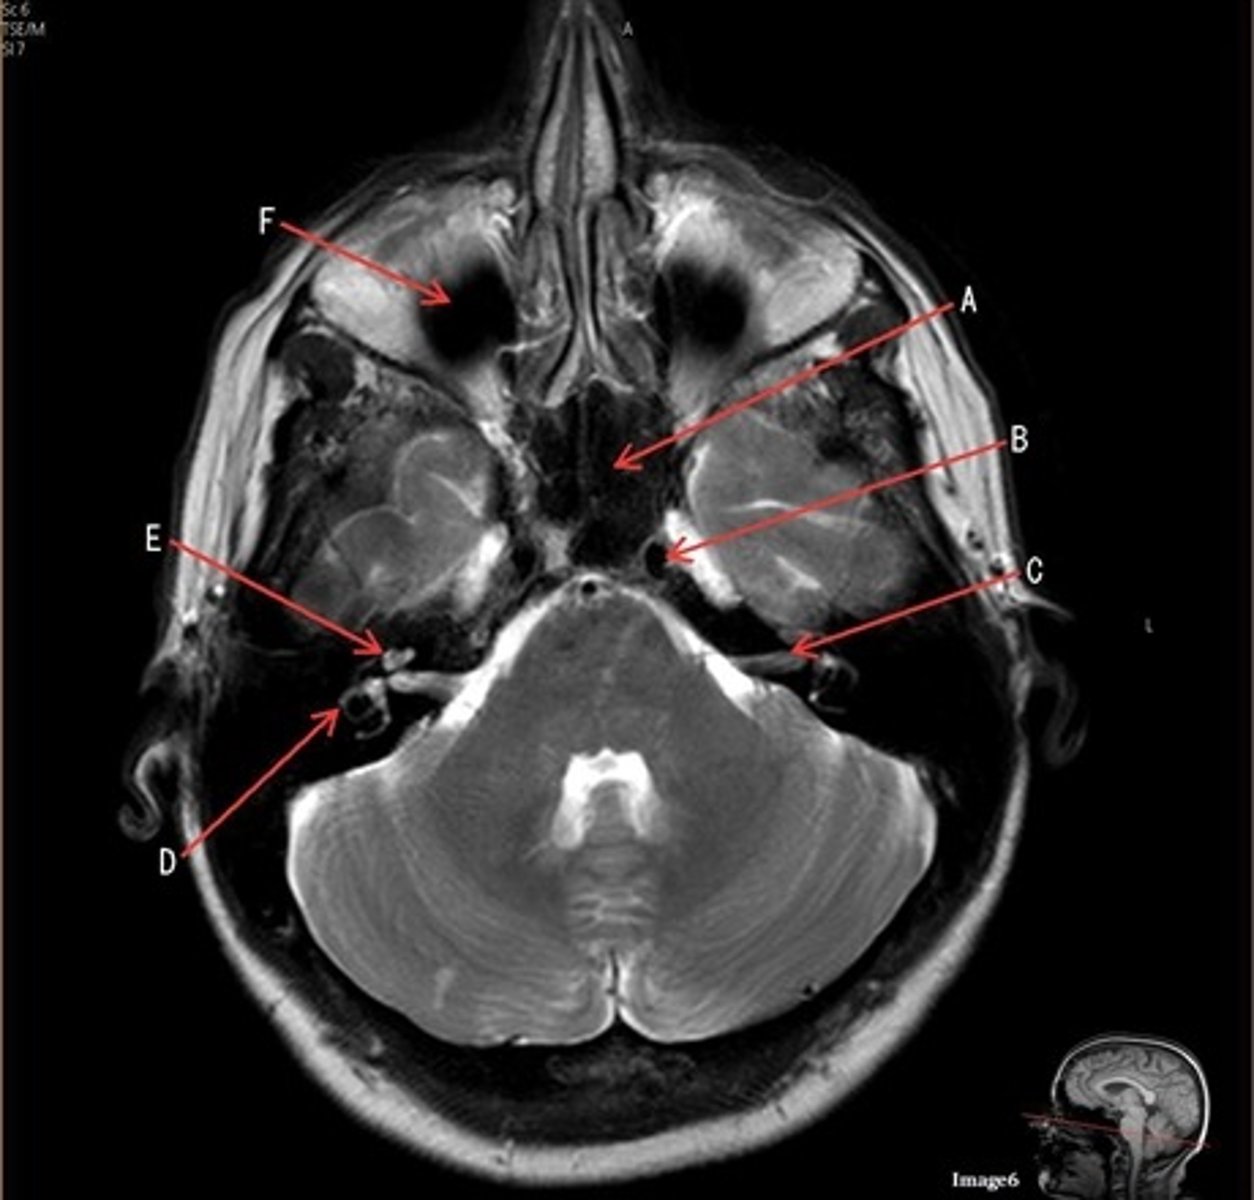

A

A- anterior cerebral artery

B

B- internal carotid artery

C

c- vertebral artery

D

D- basilar artery

E

E- posterior cerebral artery

F

F- middle cerebral artery